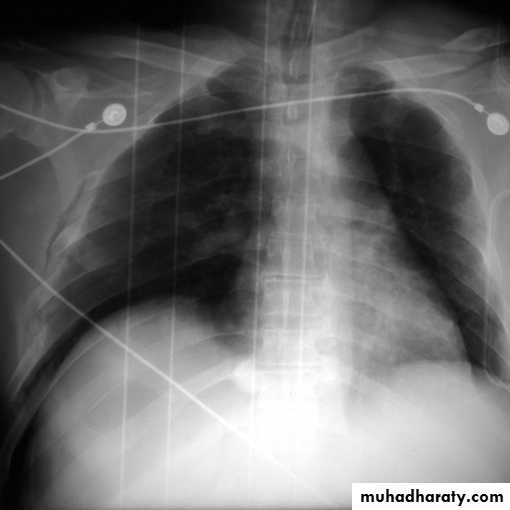

Pleural effusion in supine patient

Radiopaque hemi-thoraxPneumothorax (air in pleural space )

Signs

Loss of vascular markings at the outer parts of lung fieldsDemarcating pleural line between the lung & vessels lacking area.

Well demarcating of the scapula

Epsilateral lung collapse

Tension pneumothorax

Emergency condition

Pressure effect on the mediastinum & major vessels

Treatment by chest tubes